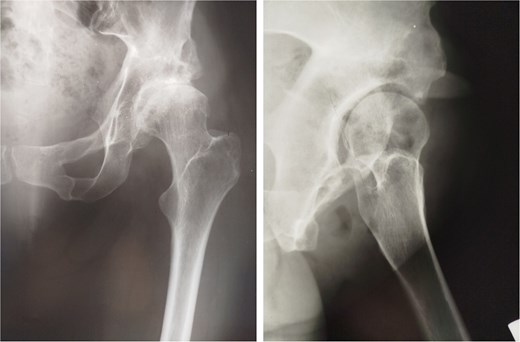

Twenty-eight years after triple osteotomy, the patient presented with painful end-stage osteoarthritis, with body mass index of 18. A hybrid cemented THA was performed using a standard posterolateral approach (Fig. 3). A cobalt-chrome femoral head was articulated with highly reticulated polyethylene liner. A press-fit cementless cup stabilized with two screws (Tylogy®, Zimmer) and a cemented straight femoral stem (Müller®, Zimmer) were implanted.

Anteroposterior radiographs of the pelvis 28 years after the pelvic osteotomy, showing advanced left hip osteoarthritis (Tönnis Grade V). A hybrid cemented total hip arthroplasty was implanted using a standard posterolateral approach.